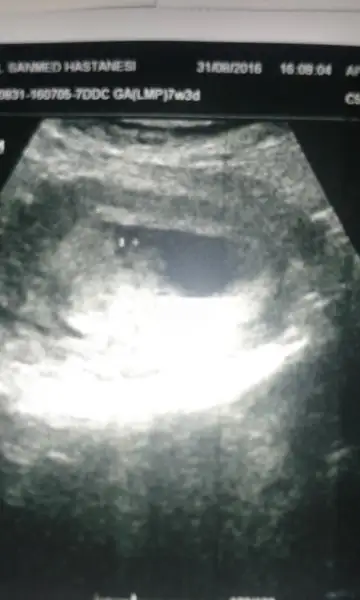

Bi yorum da benim minige rica edebilir miyiz? 7+3 batın usg. Tesekkurler:)Eki Görüntüle 1879196

Kese büyük ise kız küçük ise erkek ben geçmiş yorumlarina bakmişim.. doğru mu bilmiyorum. bazilarin tam tersi olabiliyo kişiden kişiye degişiyor.Eki Görüntüle 1879943 Kızlar bilen varsa yorum yapsın bari dundendir bekliyorum son adet tarihine göre 10 + 2 iki gün önce doktora gittim ultrasonda 11 haftalık çıktı

öle oluyormuş fasulye gibiyse erkek yuvarlak ise kızmiş:)Havalianne__ burda benim bebeğim 8+5 haftalık. Kese yuvarlaksa kız fasulye gibiyse erkek miydi. Benimki tam yuvarlak da değil tam fasulyede değil sanki. Ona göre bi bakar mısın

Karından baktı canımbenim sağda yatiyo karnimdan bakti. altinda duruyor sanirim erkek mi oluyorHavalianne__

Ben bir şeye benzetemedim canım :)Kese büyük ise kız küçük ise erkek ben geçmiş yorumlarina bakmişim.. doğru mu bilmiyorum. bazilarin tam tersi olabiliyo kişiden kişiye degişiyor.

Ben bir şeye benzetemedim canım :)